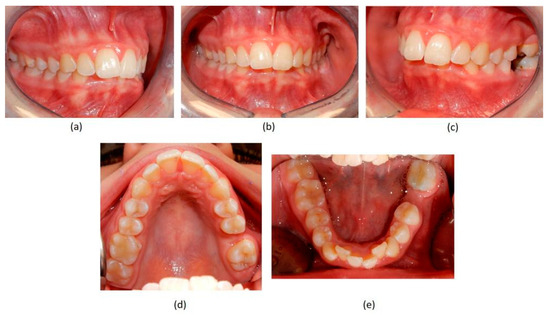

Figure 3.

Pre-treatment intraoral photographs. (a) right-side view; (b) deep bite in frontal view; (c) absence of the two first molars on the left side; (d) upper occlusal view showing the absence of the left first molar; (e) lower occlusal view showing the absence of the left first molar and the moderate crowding of the incisors.

A case of CA therapy without attachments and without the aid of hybrid elements has been documented. The patient, an 18-year-old woman at the beginning of treatment (October 2021), signed written informed consent to orthodontic treatment and authorized the use of her anonymized treatment data, including photos, X-rays and virtual models of the dental arches. She needed to rehabilitate two edentulous areas corresponding to first maxillary and mandibular molars, both on the left side, assessed as irrecoverable for destructive caries at the time of the orthodontic evaluation (Figure 1). The patient refused rehabilitation with prosthetic implants and orthodontic treatments with fixed or hybrid fixed-removable therapy. Orthopanoramic (Figure 1) and lateral teleradiography of the skull (Figure 2) were acquired to make the necessary assessments. The cephalometric examination was performed using the Cephio© Cephalometric Analysis artificial intelligence driven platform (Cephio sp. z. o. o. [Ltd.]). Her skeletal class II malocclusion was due to maxillar and mandibular retrusion (SNA 80°, SNB° 74.6°, ANB 5.4°, SNPog 76.2°). She had “long face” (OP-SNP 21.1°), a posterior inclination of the jaw (MPGoGn- SNP 35.4°), slight hyperdivergence (FMA 26.2°), with pro-inclined lower incisors (1-NB 28.4°, IMPA 96.1°) and retroclined upper incisors (1-NA 14.1°, FMIA 57.7°). Overjet and overbite were severely altered (6 and 7 mm) (Table 3). Orthodontic treatment started 4 months after the first left maxillary and mandibular molar extractions. Intraoral and facial photos were captured (Canon© Coolpix A900, Canon, Tokyo 146-8501, Japan). Dentally, she had a first molar and canine class on the right side, and a first canine class on the left side in which the molar class was no longer assessable (initially it was a first class); however, a partial reduction in edentulous spaces was observed due to the movement of adjacent teeth (Figure 3) and lower incisors were moderately crowded. Precision silicone impressions (Elite HD+ Putty Soft Normal and Elite HD+ Super Light Body, Zhermack SpA, Badia, Italy) were taken using the double technique. Then, a virtual setup of the treatment with CAs was developed to evaluate its feasibility. It showed full closure of edentulous spaces and was also discussed successively with the patient. The orthodontist clarified there were no data from the literature (at that time) to support the successful movements required with only CAs. The orthodontist and patient started treatment by agreement. The informed consent to treatment was signed. It also covered clinical re-evaluation with solutions less favorable to the patient’s preferences if the results in the middle of treatment had been clinically unsatisfactory or unfavorable. The orthodontist explained the need to intercept any treatment complications to the patient. This also related to the predictability of intermediate results for medico-legal reasons, for the mutual protection of her as a patient and of the orthodontist as a professional responsible for the therapy. Initial and final virtual models were superimposed to evaluate the movements obtained (Maestro 3D©, AGE Solutions S.r.l., Pontedera- Pisa, Italy). At the end of the therapy, new X-rays were requested and new intraoral and extraoral photos were recorded.